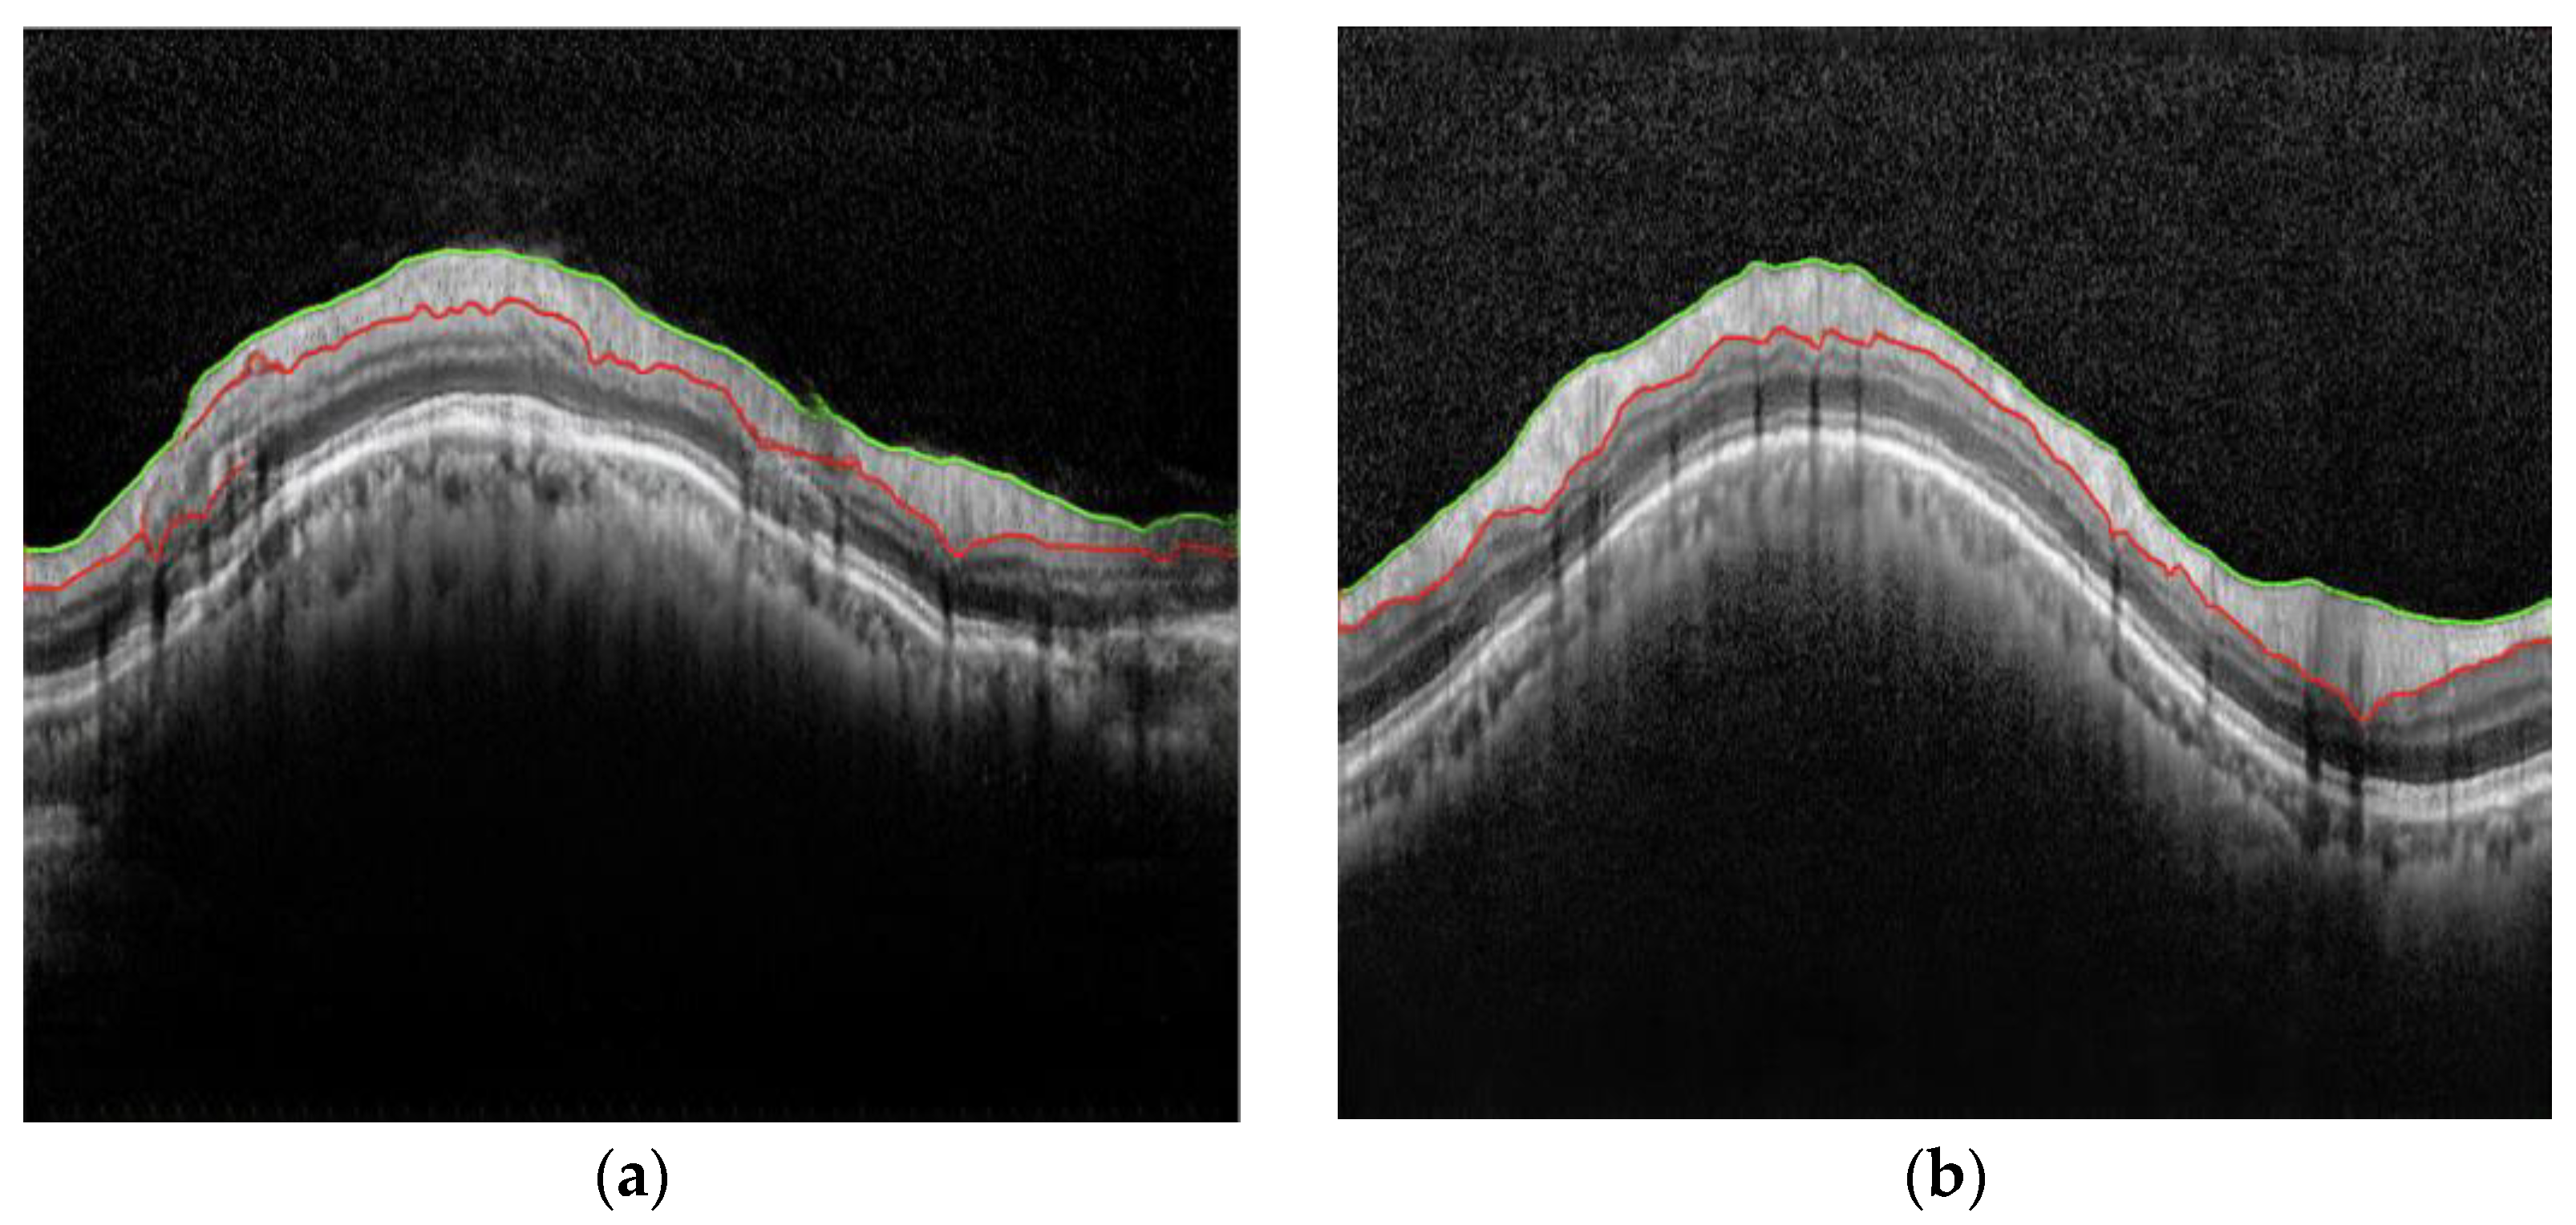

where · 2   denotes the L 2 norm, and p   denotes the total number of horizontal pixels in the images X and Y . Figure 4 provides an example illustrating the functions c ( X ) and c ( Y ) and their differences.

Figure 4. Example of c ( X ) and c ( Y ) and their differences. (a) Upper and lower layers of X; (b) upper and lower layers of Y; (c)   c X and c Y ; (d) c X c Y .